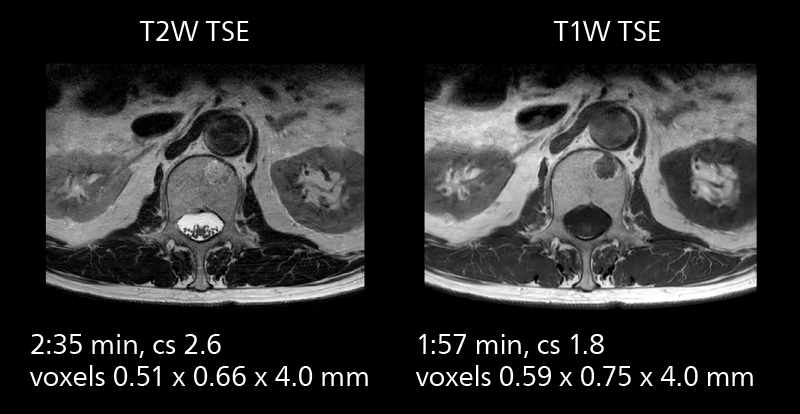

MRI of prostate

Examples of prostate imaging showing faster scan times and improved resolution illustrate the power of SmartPath to Elition X in this case of prostate cancer with PI-RADS score 4.

The high performance of the Vega HP gradients is particularly impressive in DWI. “The Vega HP gradients enable us to scan faster and use b-values as high as 2000, for example in prostate DWI and in DWIBS, which provides image quality that is remarkably improved over the previous system and we are able to more easily see lesions.”

The value of the Elition X gradients is also evident in DWIBS studies. “The fact that we can consistently obtain distortion‐free DWIBS while reducing imaging time at three coronal stations is excellent,” Dr. Makuuchi says. “In these patients, it’s also important that the application of Compressed SENSE to T2‐weighted, STIR and mDIXON sequences has no impact on the examination time of whole‐body imaging. As a result of the increased speed and higher image quality we realize, DWIBS studies have now become routine examinations.”